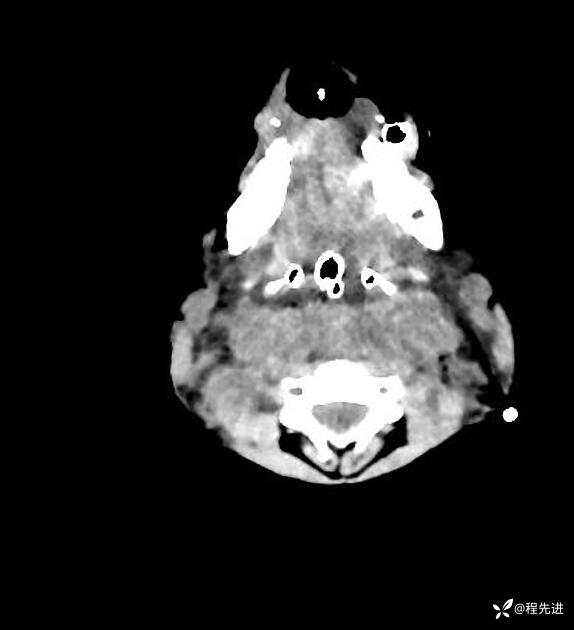

患者性别:男

患者年龄:5岁

简要病史:超速车祸外伤半小时

急诊CT平扫: